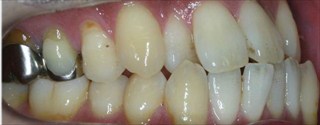

下顎前突(反対咬合、上あごの劣成長等を含む)の矯正症例

下顎前歯1本抜歯による上下前歯のバランスの改善

マウスピース型カスタムメイド矯正装置(インビザライン)単独による治療

治療後